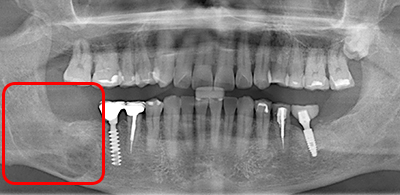

症例Case

親知らず、場合によってはこんなことも

放置していた親知らずの為に、手前の歯と顎の中に病気が発生し、2本の歯を抜歯せざるをえなくなりました。

顎の病気が大きすぎたため、顎の切断をしなければならなくなる一歩手前でした。

このような病状になる前に、早期の親知らず抜歯を推奨しております。